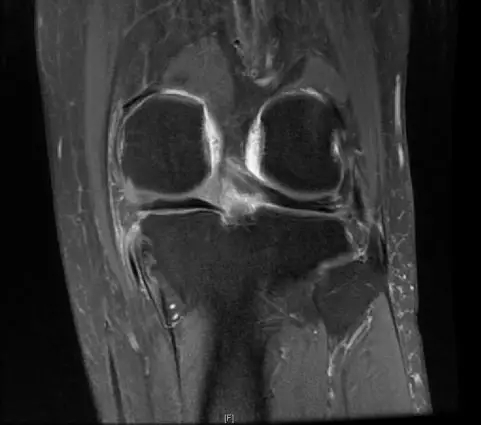

后交叉韧带断裂

从此片可以看出后交叉韧带连续性中断,松弛,增粗,下止点信号增高比较明显,从这个角度看后交叉韧带上止点信号较为正常,但下止点信号明显增高,缺乏韧带止点应有的形态,从这个层面看下止点信号增高,从这个层面看韧带是增粗的,整体信号增高,质地不均一,并且松弛,从这个层面可以看到它的下止点信号增高,缺乏正常的韧带形态特点,所以考虑后交叉韧带断裂。